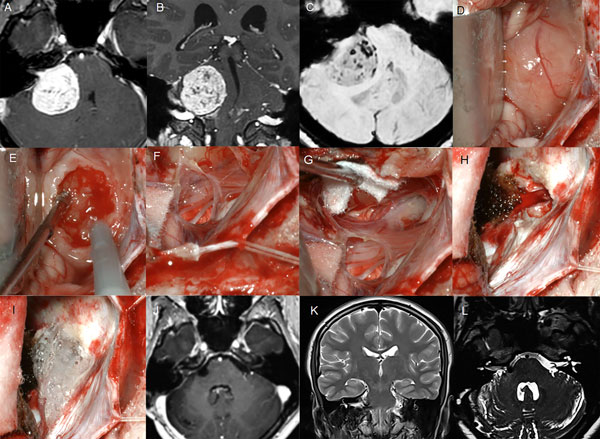

Figura 3: Paciente femenino de 40 años, operada de SV T3b izquierdo. A-B: RM preoperatoria. C-F: hallazgos intraoperatorios. G: RM postoperatoria, H: imagen intraoperatoria del lecho tumoral y descompresión del complejo VII-VIII

Figura 4: Paciente femenino 20 años, operado de SV T4b derecho. A-C: RM cerebral preoperatoria, D-I: imágenes intraoperatorias, D-F descompresión intratumoral con aspirador ultrasónico, G-H descompresión del complejo VII-VIII, I: oclusión del CAI con cola de fibrina. J-L: RM cerebral postoperatoria